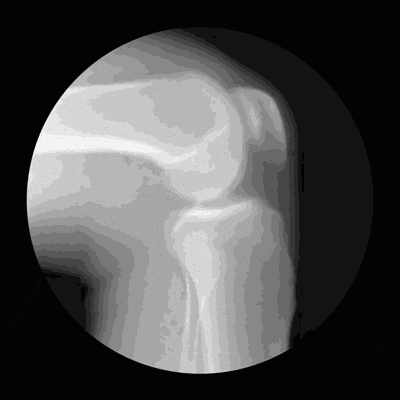

膝关节由股骨、胫骨和髌骨组成,股骨在上,胫骨在下,髌骨在表面。这三块骨头彼此对接的关节处,覆盖着一层脆弱的软骨,软骨最怕的是长时间处于压力状态。

如果膝关节长期处于压力状态,软骨的抗磨损能力就会下降,就会像图(1)这样出现软骨退化、甚至剥脱,从而诱发骨关节炎。

图(1)